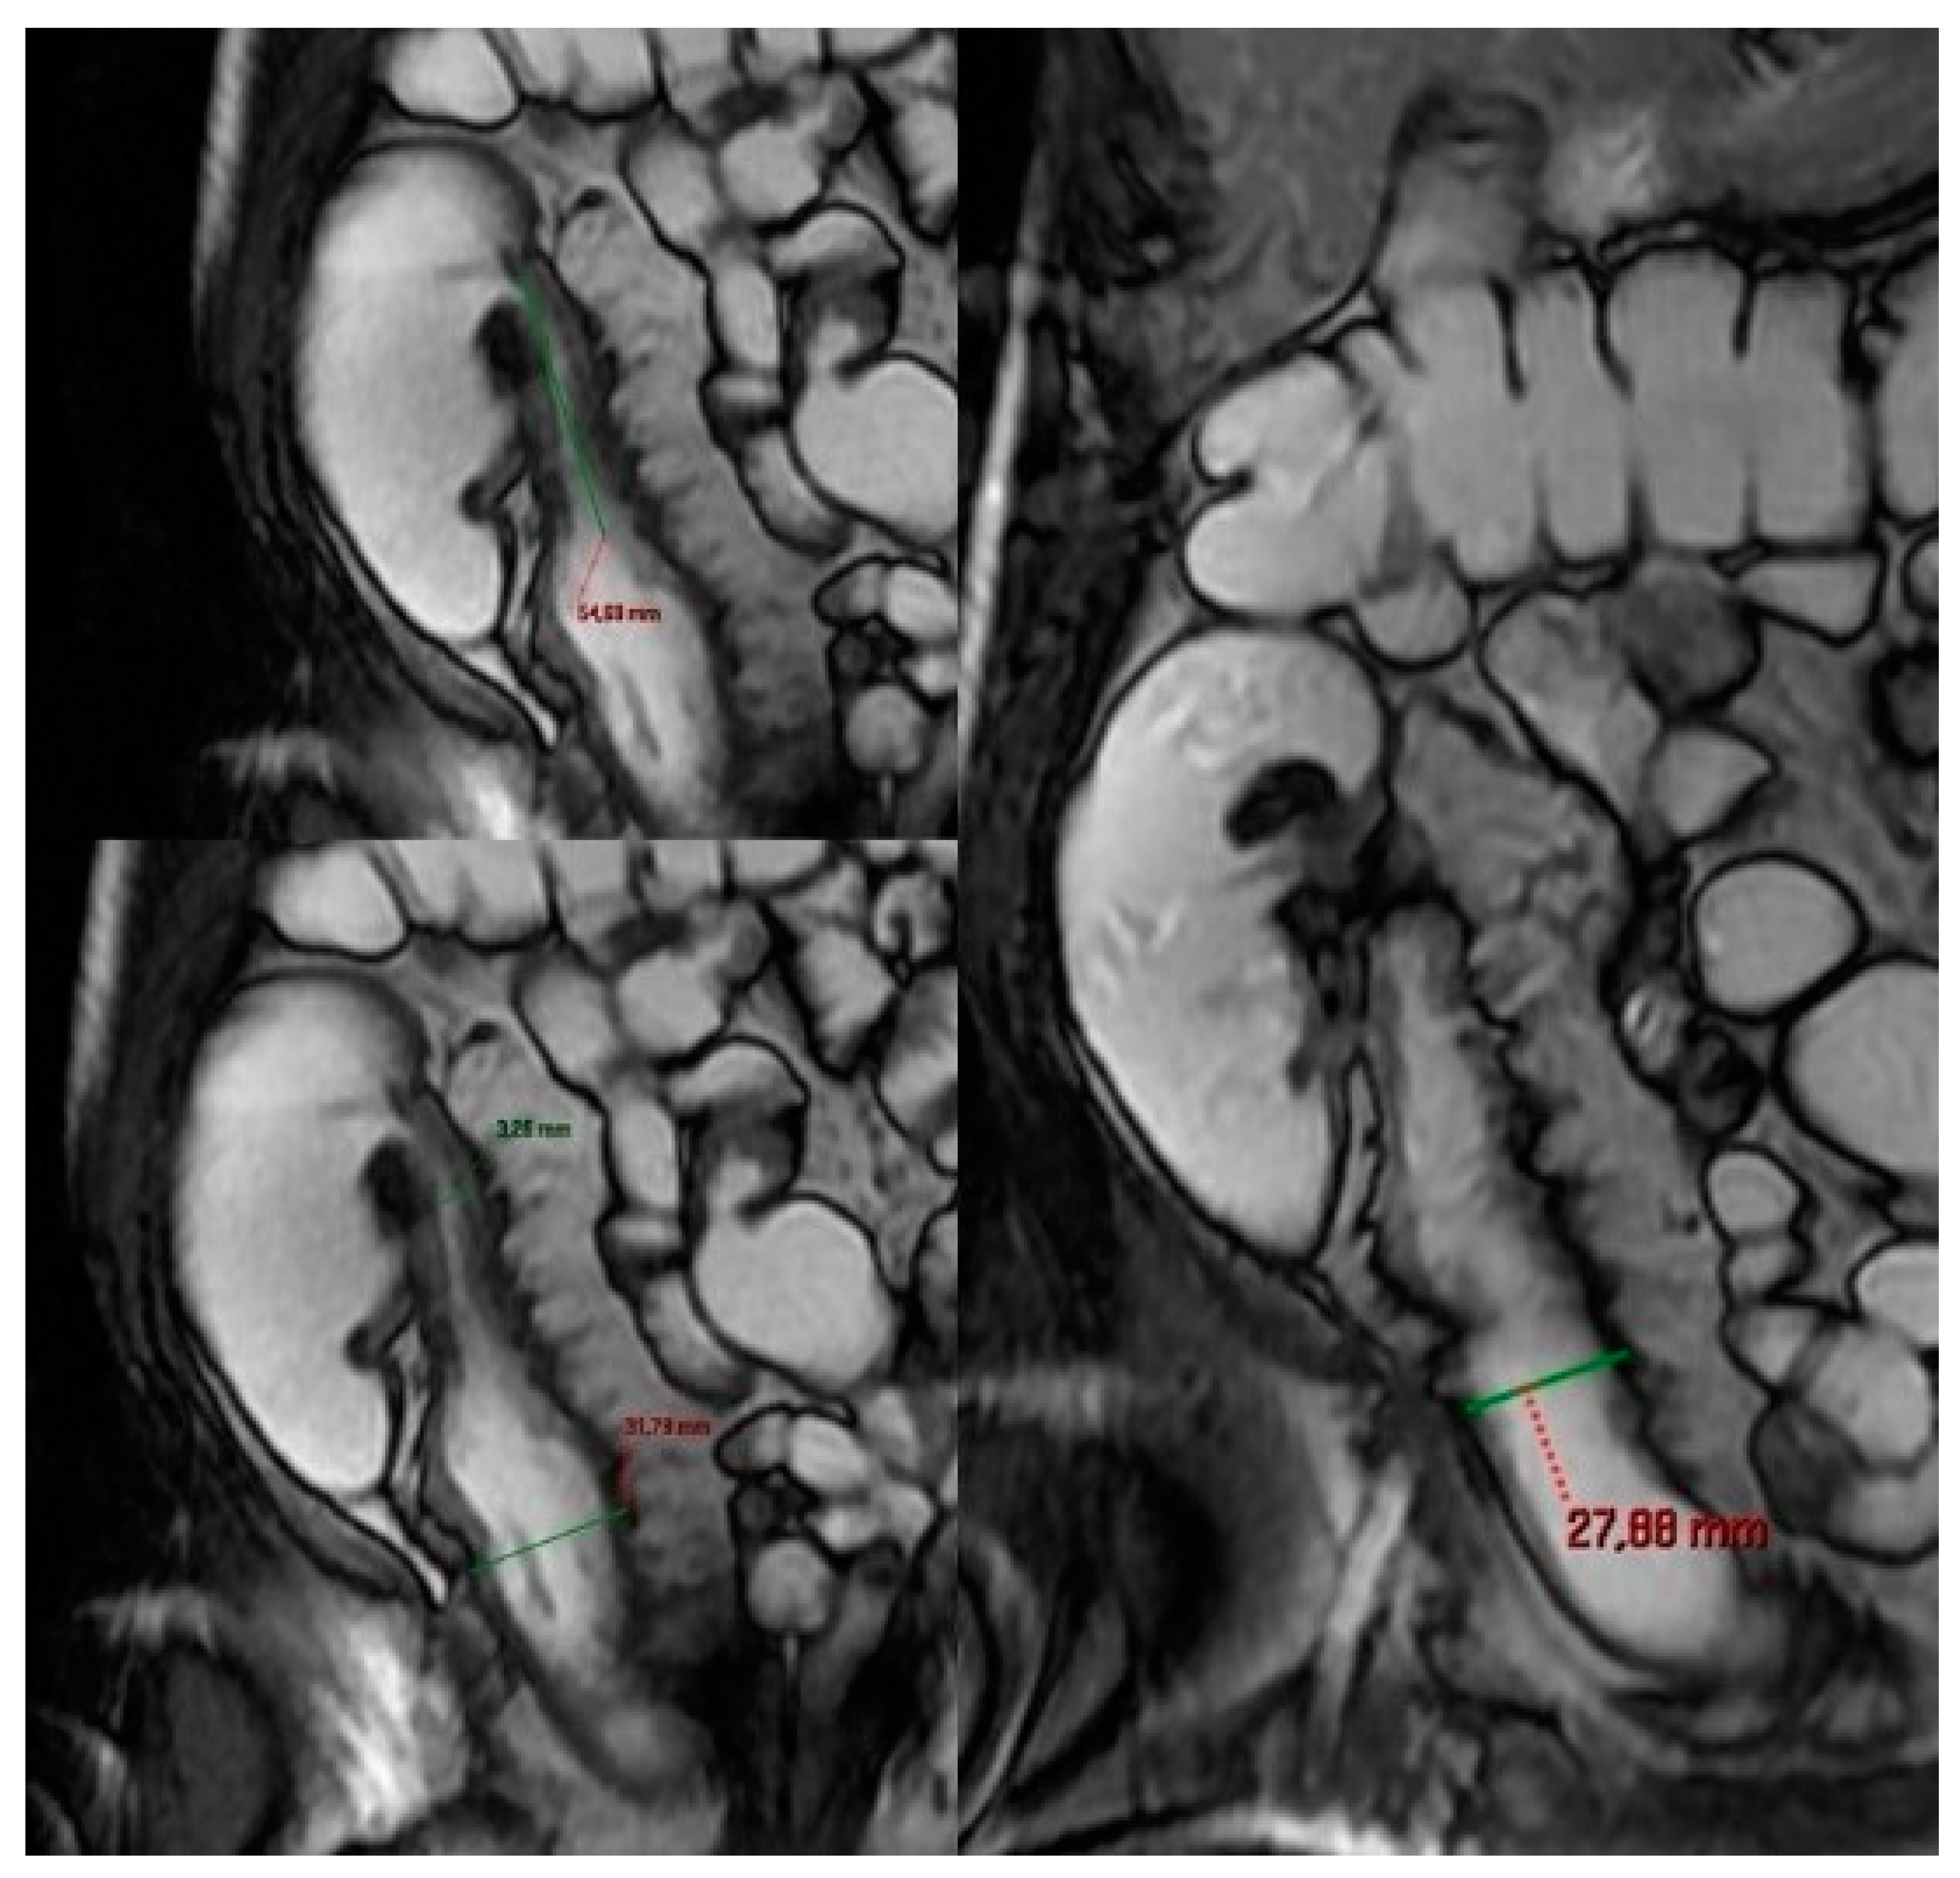

- Cronin, C.G.; Delappe, E.; Lohan, D.G.; Roche, C.; Murphy, J.M. Normal small bowel wall characteristics on MR enterography. Eur. J. Radiol. 2010, 75, 207–211. [Google Scholar] [CrossRef]

- Macari, M.; Megibow, A.J.; Balthazar, E.J. A pattern approach to the abnormal small bowel: Observations at MDCT and CT enterography. AJR Am. J. Roentgenol. 2007, 188, 1344–1355. [Google Scholar] [CrossRef]

- Guglielmo, F.F.; Anupindi, S.A.; Fletcher, J.G.; Al-Hawary, M.M.; Dillman, J.R.; Grand, D.J.; Bruining, D.H.; Chatterji, M.; Darge, K.; Fidler, J.L.; et al. Small Bowel Crohn Disease at CT and MR Enterography: Imaging Atlas and Glossary of Terms. Radiographics 2020, 40, 354–375. [Google Scholar] [CrossRef]

- Chang, C.W.; Wong, J.M.; Tung, C.C.; Shih, I.L.; Wang, H.Y.; Wei, S.C. Intestinal stricture in Crohn’s disease. Intest. Res. 2015, 13, 19–26. [Google Scholar] [CrossRef] [PubMed]